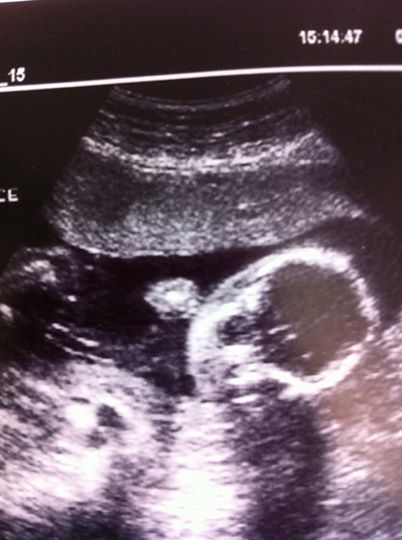

Here is what we know: Tessa has pneumonia in her left lung. We have her on an antibiotic to fight any bacterial infection that may be present and are testing for viral infections. She does not have RSV. They are doing a full panel to try to find the cause of her illness. When we were leaving the ER and headed to the PICU, she was on 100% oxygen. She’s now down to 65%. They have her on a Bubble CPAP (same type of thing used for sleep apnea). The goal today is to get her off the CPAP and onto the high flow oxygen. She has been on an IV for nourishment and they will place an NG feeding tube today so that she can get some food in her tummy. She has felt very, very hungry and, like her momma, when she’s hungry, everyone suffers. A full tummy should bring back some smiles!